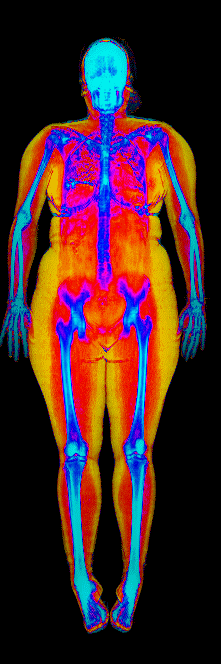

This page features real, anonymized DEXA scan images from BodyStats clients, organized by gender and body fat percentage in 5% increments. DEXA (Dual-Energy X-ray Absorptiometry) is the clinical gold standard for measuring body composition — far more accurate than scales, calipers, or visual estimates.

Each colorized scan shows the distribution of fat tissue (shown in warmer colors) and lean tissue (cooler colors) throughout the body. Compare your own DEXA scan to others in your range, or see what different body fat levels actually look like on a scan.

Female DEXA Scans by Body Fat %

30 to 35% body fat